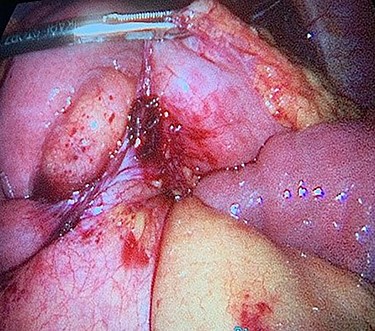

The patient taken to the operating room for diagnostic laparoscopy and proceed, after insufflating the abdomen the whole abdomen examined and showed proximal dilatation of small intestine with collapse of distal part of jejunum, the ileocecal junction identified and the small bowel examined proximally till the obstruction identified, which is fibrous band originating from the stomach to the proximal part of jejunum (Fig. 3), examination of this band showed that this band is caused by suture penetrating the stomach wall, which is going with the previous history of the endoscopic gastroplasty, reduction of the internal hernia done by releasing of the fibrous band, the herniated segment was healthy (Fig. 4).

Fibrous band originating from the stomach to the proximal part of jejunum.